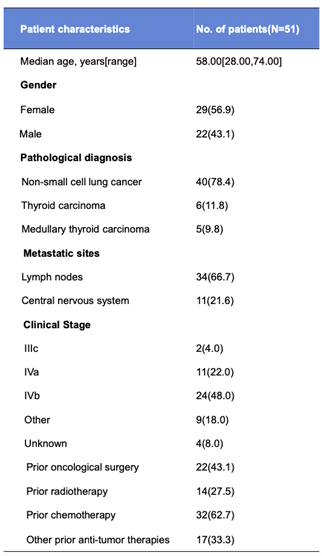

жЙАжЬЙеПЧиѓХиАЕеЭЗеЗЇзО∞еМїж≤їжЬЙеЕ≥дЄНиЙѓдЇЛеК°пЉИTRAEпЉЙ�����пЉМжЬАеЄЄиІБзЪДTRAEдЄЇASTеНЗйЂШпЉИ64.7%пЉЙгАБALTеНЗйЂШпЉИ58.8%пЉЙгАБTBILеНЗйЂШпЉИ45.1%пЉЙгАБWBCйЩНдљОпЉИ43.1%пЉЙгАБNEUTйЩНдљОпЉИ33.3%пЉЙгАБйЂШе∞њйЕЄи°АзЧЗпЉИ31.4%пЉЙгАБйЂШи°АеОЛпЉИ29.4%пЉЙгАБдљОзЩљиЫЛзЩљи°АзЧЗпЉИ25.5%пЉЙгАБSCrеНЗйЂШпЉИ23.5%пЉЙеТМе§ізЧЫпЉИ23.5%пЉЙ[1]����гАВ

BYS10зЪДйЬ≤еЗЇйЗПдї•еЙВйЗПдЊЭиµЦжАІзЪДжЦєеЉПдїО25mgеҐЮйХњеИ∞600mg����гАВеЕґдЄ≠�����пЉМ100 ~ 300 mg BIDзїДж±ЗжК•зЪД3 ~ 4зЇІTRAEпЉИпЉЮ5%пЉЙиХіеРЂASTеНЗйЂШпЉИ25.5%пЉЙгАБALTеНЗйЂШпЉИ13.7%пЉЙеТМйЂШи°АеОЛпЉИ9.8%пЉЙ����гАВдЄ•ж≤ЙдЄНиЙѓдЇЛеК°7дЊЛ[1]����гАВ